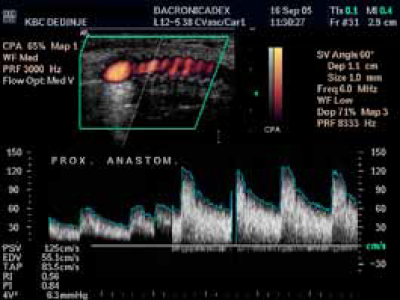

Karotidna restenoza se nekad mora korigovati interpozicijom by pass grafta (Dacron).

Rekonstrukcija bifurkacije sa dakronskim graftom zbog restenoze.

Uredan nalaz Spektralna analiza